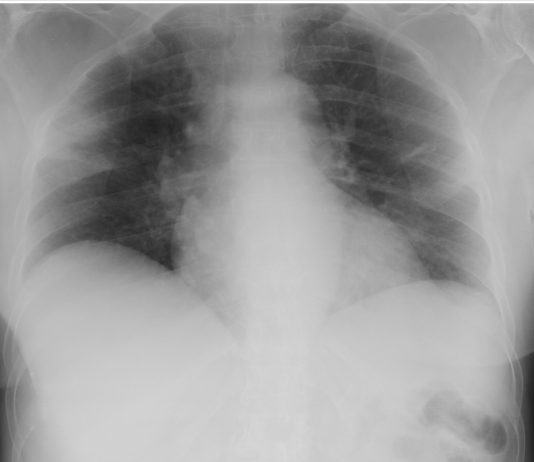

Stefania Ianniello, Michele Galluzzo, Riccardo Ferrari, Margherita Trinci, Stefano Giannecchini, Carmelo Rende, Viola Valentini, Riccardo Palliola. Diagnostica per Immagini nell’Emergenza Urgenza - Azienda Ospedaliera San Camillo-Forlanini, Roma

Paziente di 80anni, cardiopatico, iperteso, esordio con febbre elevata, dispnea e tosse.